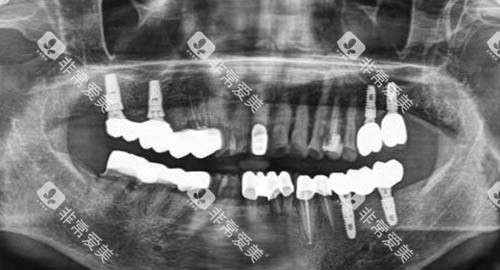

张医生:种植牙医师,15年临床经验,已完成上千例种植手术,尤其擅长复杂病例的处理。

初诊检查:医生会进行详细的口腔检查,必要时拍摄X光片。